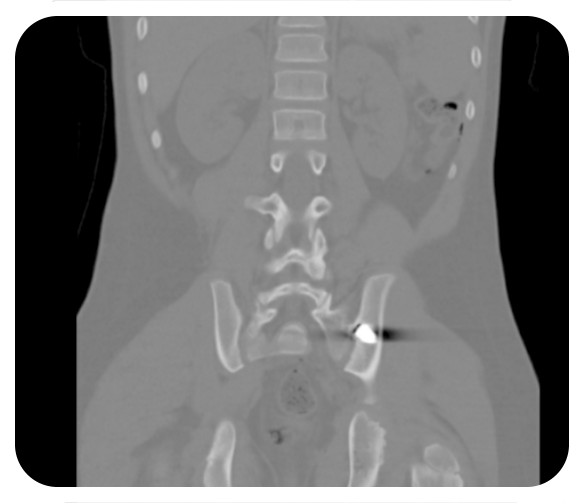

La fractura por estrés de la columna posterior puede ser una complicación poco reconocida después de la osteotomía periacetabular (PAO), y la técnica quirúrgica puede influir en la tasa.

- Los objetivos de este estudio fueron caracterizar la incidencia y los factores de riesgo asociados con las fracturas por estrés después de la osteotomía periacetabular y determinar su efecto sobre la consolidación de la osteotomía.

- La fractura por estrés de la columna posterior puede ser una complicación poco reconocida después de la osteotomía periacetabular (PAO), y la técnica quirúrgica puede influir en la tasa. Se debe considerar el uso de un cincel estrecho durante el corte isquiático para reducir el riesgo de propagación de la tensión a través de la columna posterior.